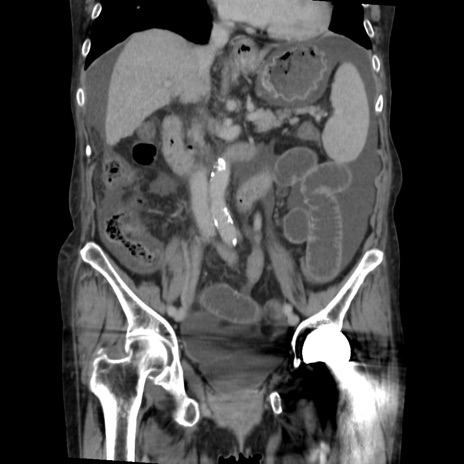

症例31(冠状断像)

横断像